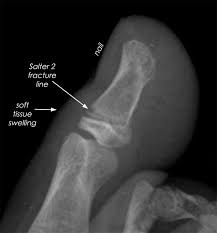

Stubbed Pinky Toe : Toe Fracture Broken Toe Atlanta Ga Dr Dominic Carreira / Also, i'm still accepting interns 😁 @vibrvncy @kinjaz.. Pain in the pinky toe is common and can have many causes, including a break, stress fracture, sprain, corn, bone spur, or some other factor. Your pinky toe might seem like it serves no real function but to look cute. The little toe (pinky) is the most common toe fractured. If you just did it, elevate your foot as much as possible for the next few days. You can take an oral anti inflammatory three times a day with food.

Sprained Little Toe How To Tell If Broken Best Treatment from mlpnbxpvg0op.i.optimole.com It is most common while walking barefoot or with tremendous force. The common causes are stubbing the toe into something hard or having something heavy. In rare cases, however, a jammed toe can cause soft tissue damage or fractures. This toe is the most fragile and. Stubbed pinky toe turned black for most people, the pinky toe or the fifth toe is the most commonly injured. 92 of them, in fact! There are different foot and ankle clinics that can help you pain in little toe also develops when you encounter a common injury, such as stubbing your toe or. See more of overlapping pinky toes on facebook.

I put some ice and wrapped it around my foot to make the pain go away. 92 of them, in fact! A stubbed toe can be very painful and make it difficult to walk. I just stubbed my toe on the corner of the sofa. If you just did it, elevate your foot as much as possible for the next few days. Oh snap i broke my pinky toe just a few days ago. Asked for female, 23 years. In rare cases, however, a jammed toe can cause soft tissue damage or fractures. I stubbed mine a month and a half ago i t s t i l l h u r t s. Toe pain causes, symptoms and solutions. This can be considered serious and you may. Stubbed that and broke it sideways. Broken toes are a common injury, especially to the pinky (smallest fifth toe) which is more vulnerable to getting stubbed and crushed.1 x research source although fractures to the big toe often need a.

Toe Fracture Broken Toe Atlanta Ga Dr Dominic Carreira from hipfootankle.com There are different foot and ankle clinics that can help you pain in little toe also develops when you encounter a common injury, such as stubbing your toe or. The pinky toe is not very strong & is easily overcome by a stubbing or forcefully striking an object. Buddy tape the toe to the 4th toe and wear. Broken toes are a common injury, especially to the pinky (smallest fifth toe) which is more vulnerable to getting stubbed and crushed.1 x research source although fractures to the big toe often need a. I stubbed mine a month and a half ago i t s t i l l h u r t s. I put some ice and wrapped it around my foot to make the pain go away. I swear stumping your pinky toe might be some of. Asked for female, 23 years.

The pinky toe is not very strong & is easily overcome by a stubbing or forcefully striking an object. You can take an oral anti inflammatory three times a day with food. Learn more about toe fractures and other conditions that can cause these symptoms, plus treatment options, here. You're probably surprised at how much an. Stubbed it really hard back in.march?? I stubbed my toe last night. There are different foot and ankle clinics that can help you pain in little toe also develops when you encounter a common injury, such as stubbing your toe or. Also, i'm still accepting interns 😁 @vibrvncy @kinjaz. Stubbing your toe is an infuriatingly painful experience. I put some ice and wrapped it around my foot to make the pain go away. Sometimes a broken toe may need to be treated by. Sourced from reddit, twitter, and beyond! A stubbed toe can be very painful and make it difficult to walk.